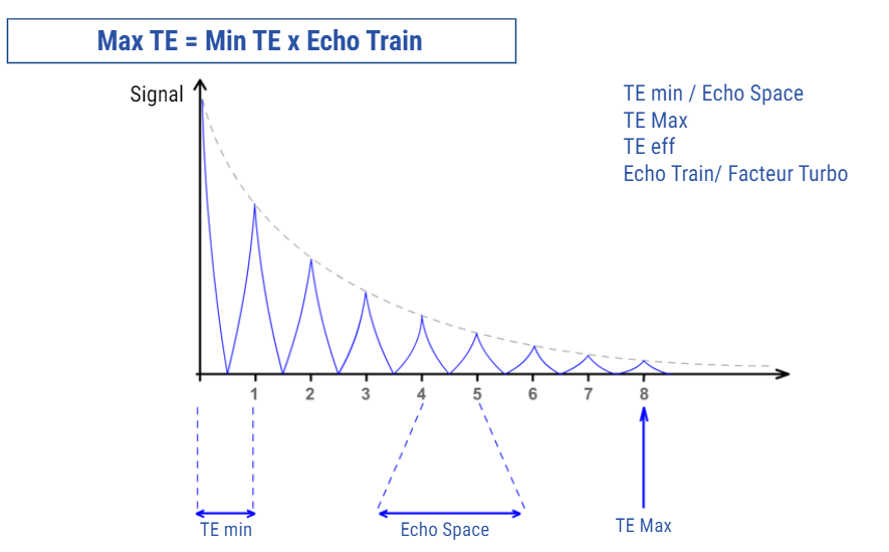

The time between the end of receiving a signal for an image, or MAX TE, and the moment of application of the 90° pulse (TR) is used to obtain a second diagram or a single echo, with the same parameters. In fact, the number of slice diagrams allowed per slice depends on the TE Max and the TR.

It is possible to change the size of the Max TE and the TR and visualize its impact on the number of slice diagrams obtained. If the TR is an easily accessible and comprehensible parameter, this may not be the case with the Max TE which does not directly respond. Besides, the parameters that impact Max TE are not the same and are based on the device. By increasing the TR or decreasing the Max TE, we can obtain more slice diagrams in a single acquisition.

The Maximum TE

The Max TE corresponds to the last echo in the echo train. In fact, its value corresponds to the time that separates the echoes, the time between echoes or TE, multiplied by the number of echoes obtained at each TR (ETL). This Max TE is not a parameter that can be accessed directly but it can be indirectly modified by modifying the echo train or by modifying the minimum TE. Based on the manufacturers, the parameters that affect the Maximum TE might not be the same. In fact, they don’t all adopt the same philosophy in terms of the automation changes.

When the difference between the weight of the echo that fills the center and the echoes that fill the periphery is too large, this blurring artifact appears. In an optimum setting, the Max TE should not be more than double the TE eff minus the TE min.

Optimizing the Effect:

To reduce the blurring artifact, the effective TE must be in the center of the echo train. Based on the manufacturers, the parameters are more or less automated. Some systems automatically alter the values of inter-echo space so that Max TE is double the Effective TE. Some allow full control, which implies a knowledge of this problem. Some others still leave some room for maneuver or adjustment to parameters.

- TEmax = TEmin * ETL